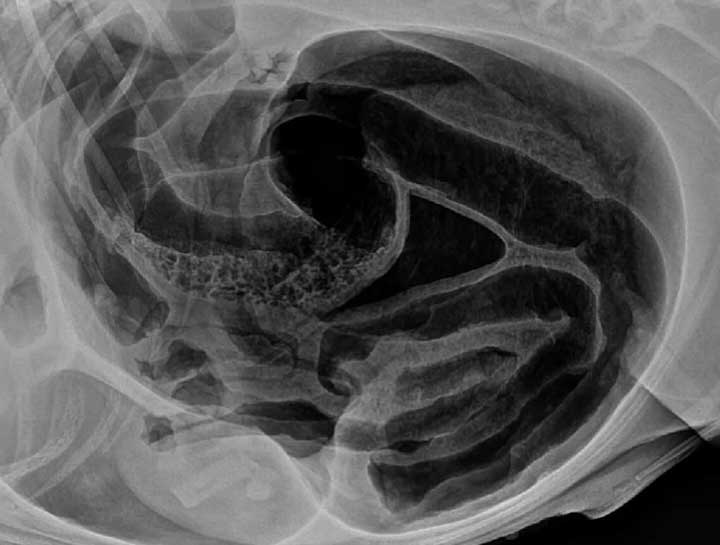

Canine Bloat

Bloat, stomach torsion or twisted stomach